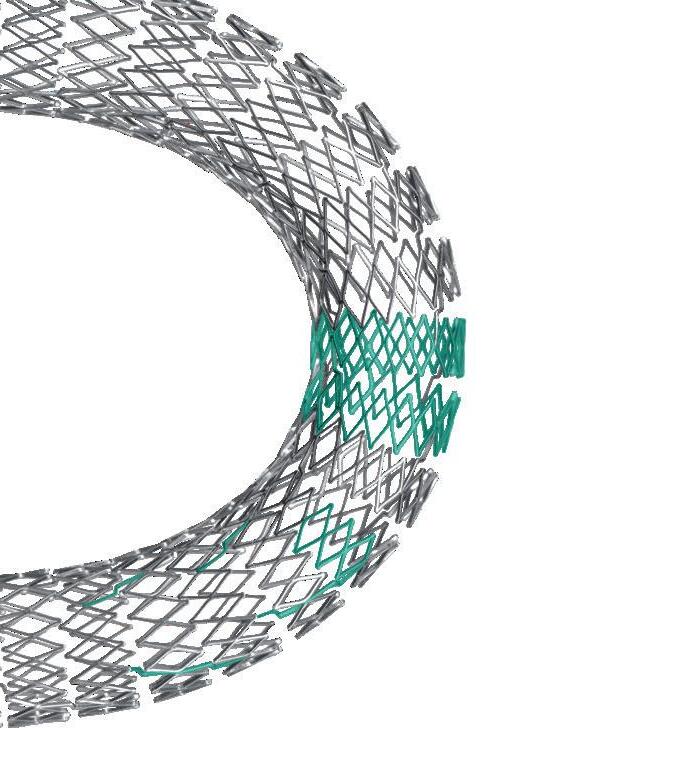

In the ongoing endovascular era, Thompson put forward, several innovations—including bioresorbable stents and non-invasive devices—have refined, or are set to refine, longstanding techniques and technologies. Indeed, the presenter said, there is “still room” for endovascular innovation despite the largely unchanging nature of its fundamental building blocks. However, these innovations will not, in Thompson’s view, ‘change everything’ in vascular surgery. Instead, he argued that the next paradigm shift in the field will be defined by the accelerated pace of technological change that is happening in the wider world.